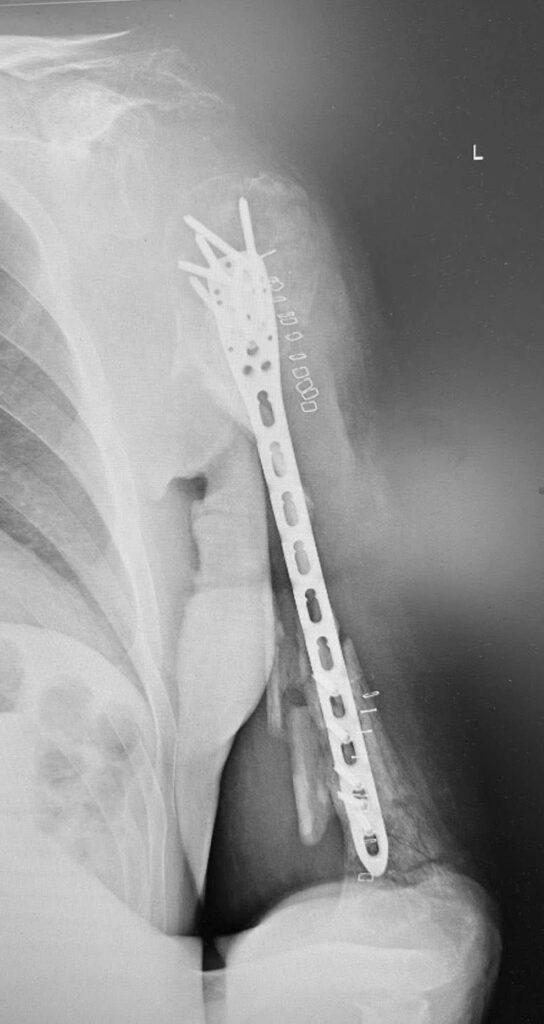

Возможно, что вы помните примерно двухнедельной давности наш с друзьями пост «Ампутировать или сохранять?». Речь шла о буквально разрушенном плече у воина ЗСУ в результате минно-взрывного ранения.

На первых этапах несколько великолепных и эффективных операций коллеги из института им О.О. Шалимова выполнили. В том числе и пластику торакодорзальным лоскутом. На видео как раз рука после этих этапов реконструкции.

А дальше пришел наш черед. Сразу выполнять и фиксацию, и пересадку кости мы не стали. Почему? Клебсиелла раньше в ране жила. А это страшная бактерия, что все труды разрушает. Как кариес зуб – вот так же точно «сгрызает» кость. Особенно «любит» только что пересаженную.

Поэтому сначала выполнили только фиксацию из малых доступов. И взяли ткани «на посев». Сеяли и на аэробные, и на анаэробные бактерии.

Никакого роста. Всё стерильно.

Поэтому следующим этапом мы (доктора Долгош Д.В., Никитин П.В., Парий В.Б. и ваш покорный слуга) взяли 12 см малоберцовой кости (свободный трансплантат) и кортикальную кость из бедра пациента с помощью RIA-2. Как раз этот этап на фото. Черно-белом, чтобы Фейсбук меньше возмущался. Там в фильтре-боксе как раз костная крошка из бедра видна. А она, как вы понимаете, красного цвета . Всё это перемешали еще и с BONALIVE (заменителем кости нового поколения с антибактериальным эффектом) и имплантировали. С ещё одной дополнительной пластиной.

Так что вот такой у нас праздник праздничный.

Поэтому вместе с фиксацией этой реально разрушенной плечевой кости (см рентгенограмму) пластиной из минидоступов, мы с Vasyl Parii и Денисом Долгушем не стали одномоментно делать и массивную костную пластику. Взяли ткани снова на посев. Если посев будет стерилен, то следующим этапом сделаем пластику. Если нет, – то вновь проведем антибактериальную мощную терапию.

Затем предстоит вмешательство на плечевом сплетении (есть повреждение). Когда (если) всё пройдет успешно, то вместе с пациентом решим, что делать с плечевым суставом. Скорее всего его замыкание (почти нет дельтовидной мышцы и элементов вращательной манжеты; не знаем объёма восстановления сплетения (положительная динамика есть)).